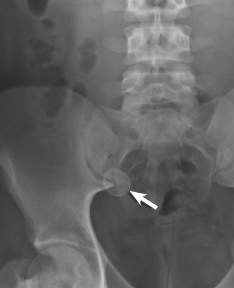

appendicitis

Magda Mendez, MD, FAAP; Dinushan Kaluarachchi, MD

<p><img src="/sites/default/files/transfer/Screen_Shot_2012-12-13_at_2.18.15_PM.png" alt="appendicolith" title="appendicolith" style="float: left; margin-left:...